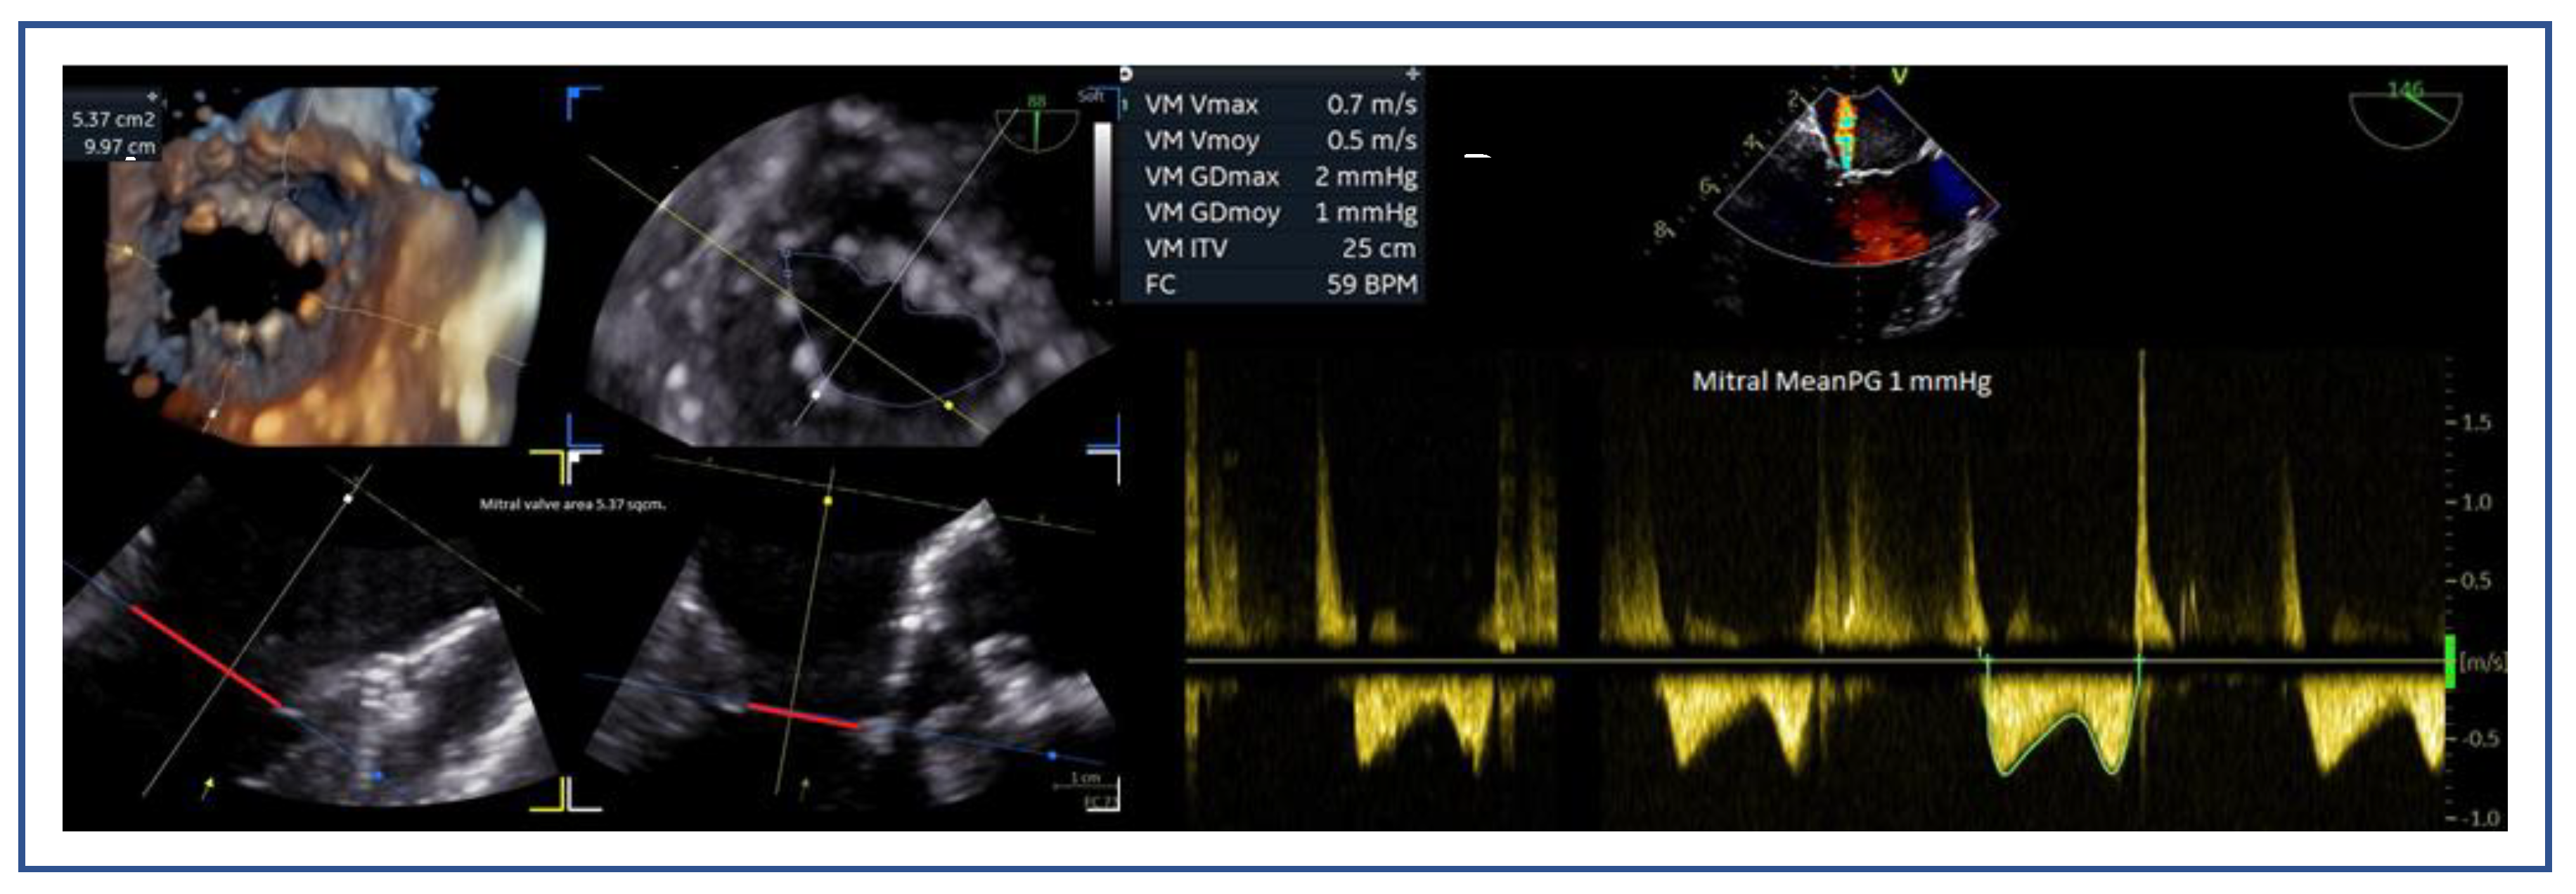

- Mitral valve area (MVA) and pressure gradient (PG): MVA <4.0 cm² may raise concern for post-procedural mitral stenosis, especially in patients requiring multiple devices. Cut-off values of 3.0cm2 for MVA and 4mmHg for mean PG are used to consider a patient ineligible for this method.

7.3. Mitral Valve Area and Gradient